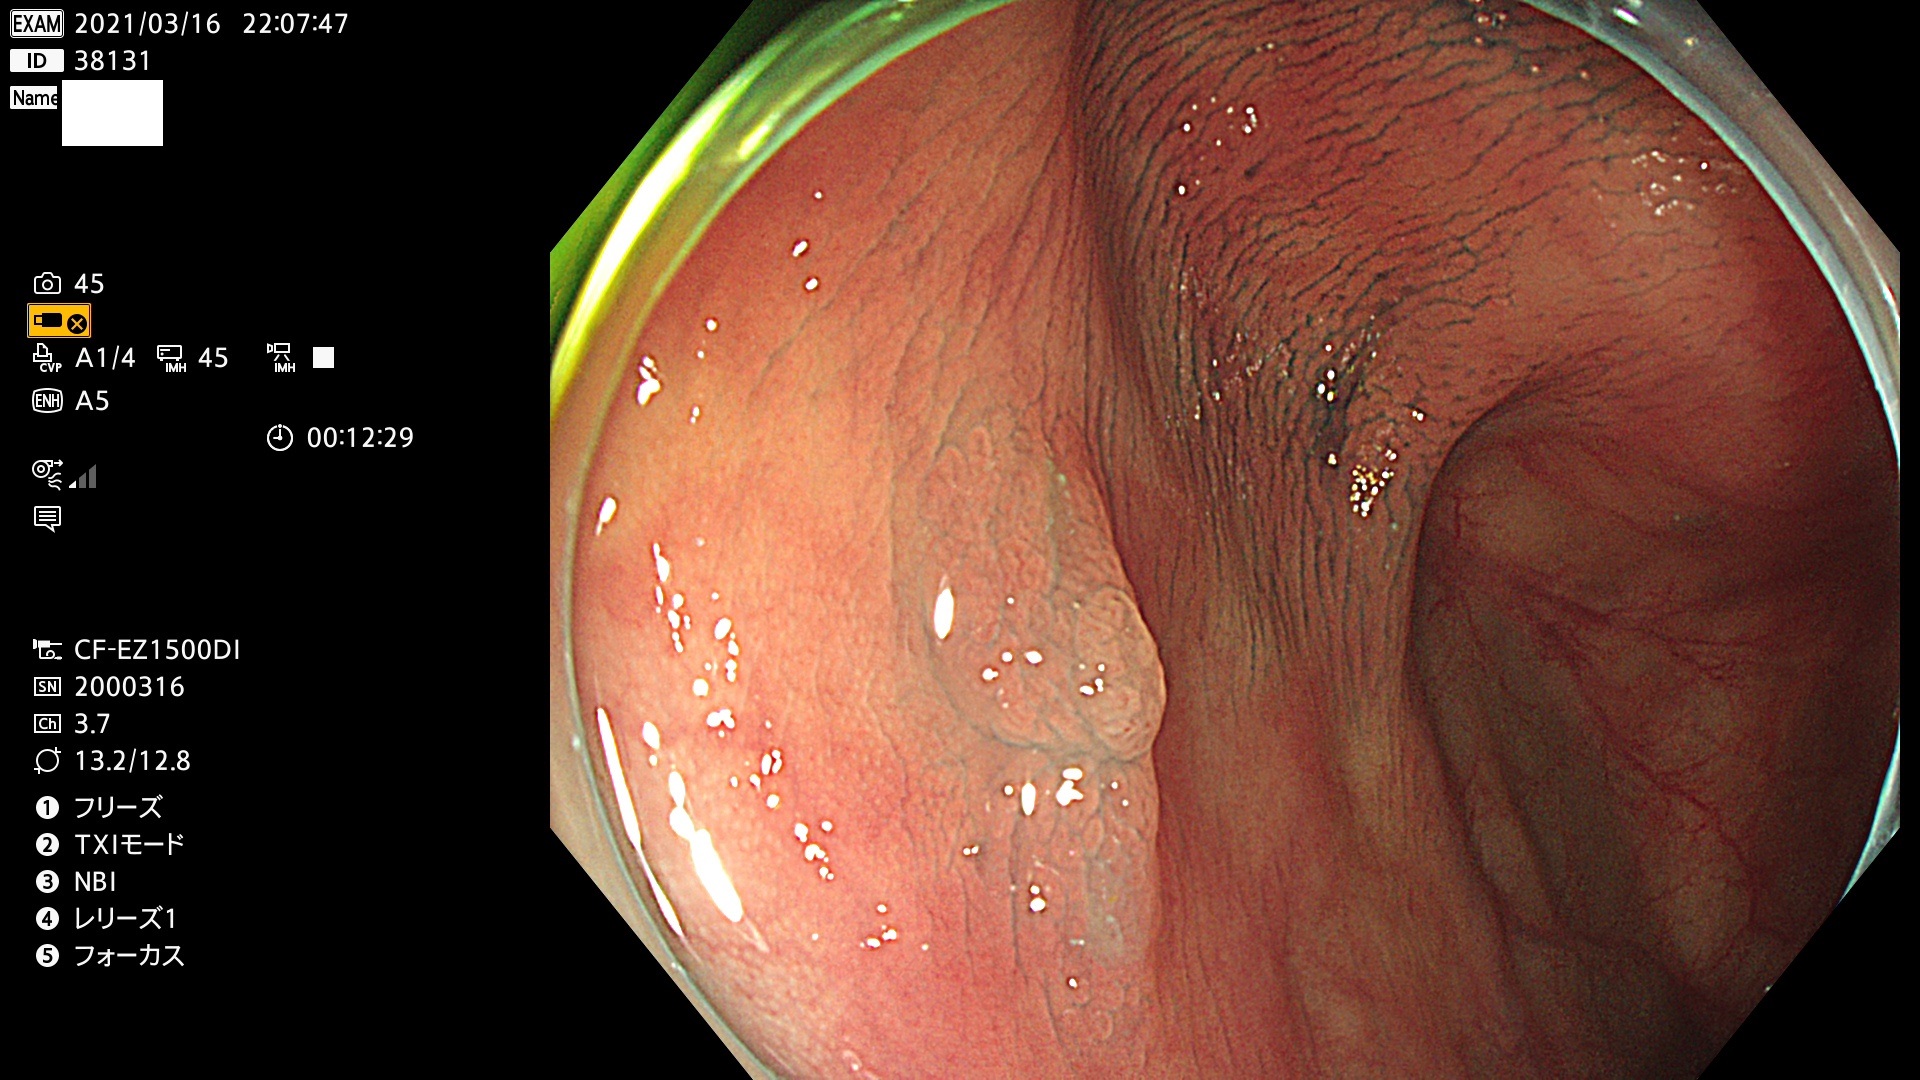

腺腫発見率 72 % (カルテ番号 38100〜38199の100名の方の検査結果で集計)大腸癌検診最新情報

以下のカルテ番号の方に腺腫(Adenoma,Group3〜5)が見つかりました(集計法)

38101 38103 38104 38106 38107 38108 38109 38110 38111 38112 38113 38114 38115 38117 38118 38122 38123 38124 38125 38126 38127 38128 38130 38131 38132 38135 38137 38138 38140 38141 38142(SSAPのみ) 38143 38144 38145 38146 38147 38148 38149 38150 38151 38152 38153 38154 38157 38158 38160 38161 38162 38164 38165 38166 38167 38168 38169 38172 38176 38177 38178 38181 38182 38183 38184 38187 38189 38190 38191 38192 38193 38194 38195 38196(SSAPのみ) 38198

発見困難で危険性の高い平坦型病変(上記100名より抽出) ![]()